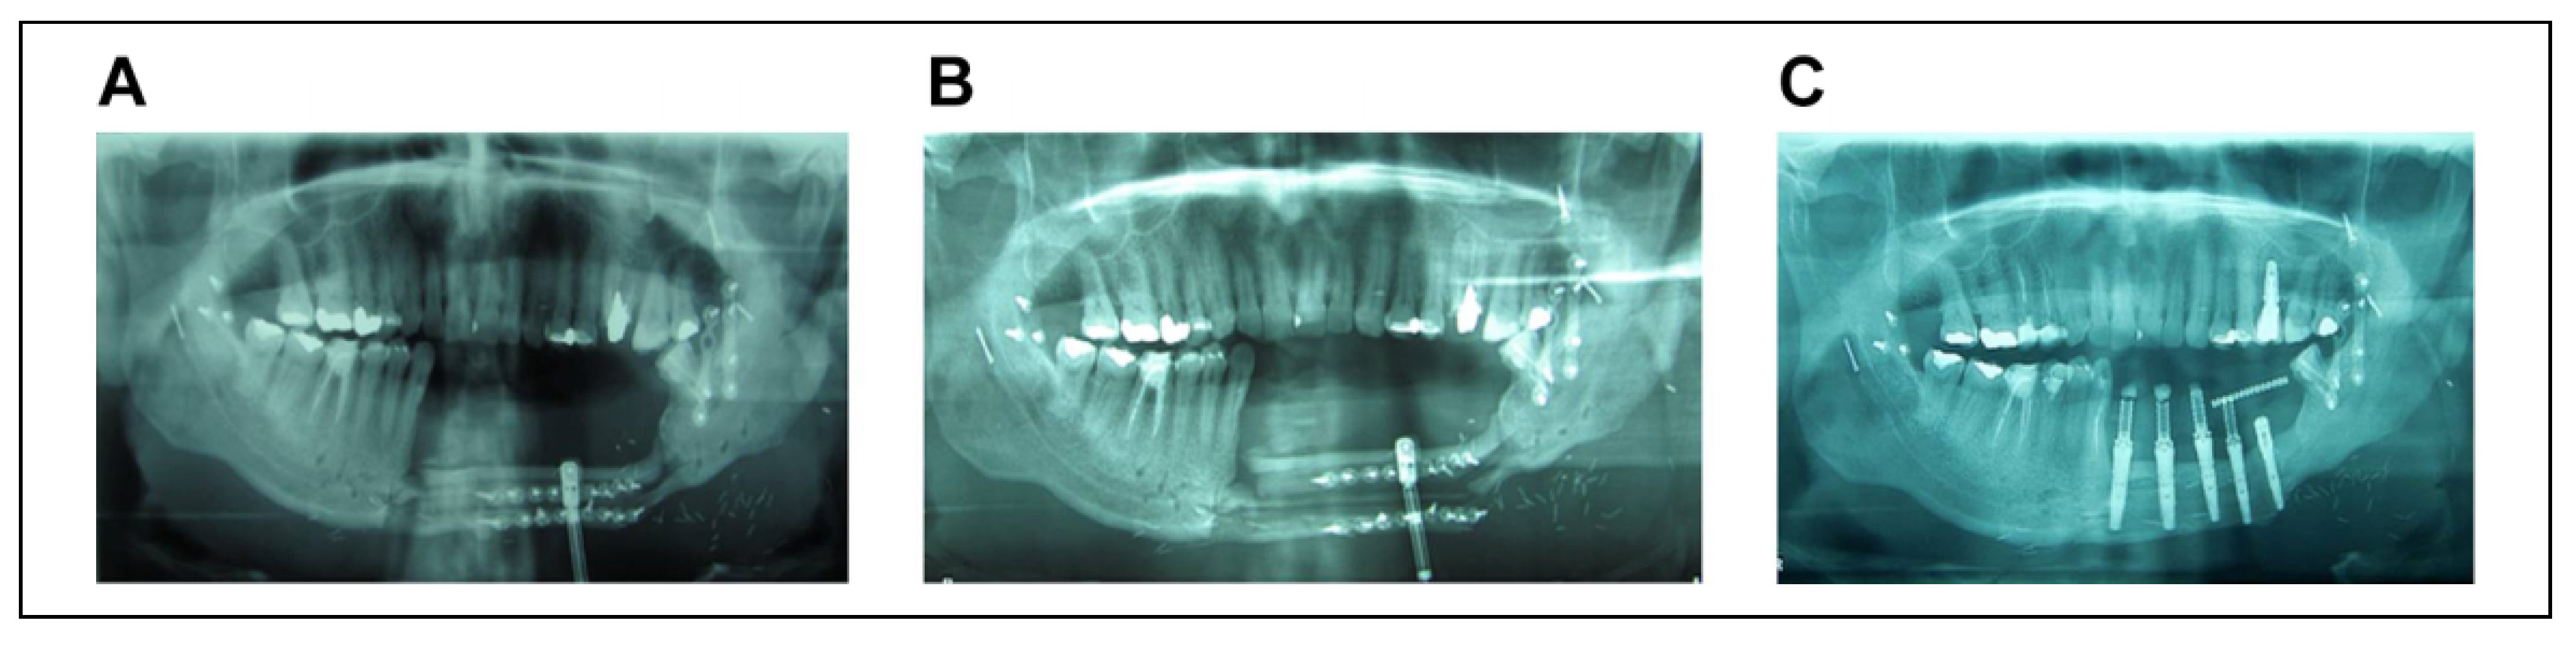

The patients who had a deficit of bone tissue in a vertical or transverse plane, underwent osteogenic distraction in order to correct either the length or width of the bone, respectively. Once an adequate bone measure was achieved and the distractor was removed, these patients underwent placement of osseointegrated implants (Figure 2) at a later stage after their rehabilitation.

Figure 2. A. Osteogenic distraction performed to correct width of bone. B. Completed osteogenic distraction. C. Placement of osseointegrated implant.